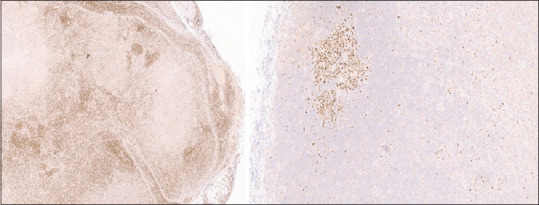

Abstract: Cervical lymphadenopathy can be due to numerous causes. The common causes include reactive and infections conditions in children and malignancy in the elderly. Kikuchi-Fujimoto disease (KFD) is a rare cause of cervical lymphadenopathy. As viral vaccines contain viral antigens, they can trigger the development of KFD. The human papillomavirus (HPV) vaccine can trigger KFD. It is important to elicit a history of prior vaccination to identify the trigger in patients with necrotising histiocytic lymphadenitis suspected of having KFD. We hereby report a case of a 16-year-old female who was diagnosed with HPV vaccine induced KFD. Ours is the first case to be reported from India. Histopathology revealed necrotising histiocytic lymphoid hyperplasia and the absence of neutrophils, eosinophils, plasma cells, vessel wall vasculitis, haematoxylin bodies, and Reed-Sternberg cells, and negative aerobic, MTB cultures, anti-nuclear antibodies, clinched the diagnosis of KFD.

Abstract Image